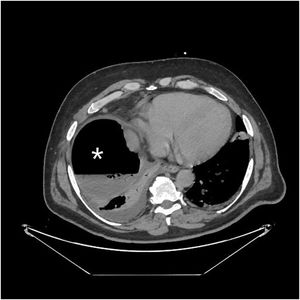

Varón de 49 años, sin antecedentes salvo por una tumorectomía renal derecha laparoscópica realizada hace un mes, por quiste Bosniak III-IV. Se presenta en urgencias con malestar general, dolor abdominal inespecífico y disnea. Se realiza inicialmente una radiografía de tórax (fig. 1), la cual es sugestiva de neumoperitoneo, seguida de un TAC abdominal (fig. 2) que muestra una colección subfrénica con nivel hidroaéreo. Durante la intervención quirúrgica se confirma una perforación de colon derecho retroperitoneal. Aunque las perforaciones de colon retroperitoneal suelen acompañarse de retroneumoperitoneo y abscesos retroperitoneales, en este caso no se identifican ninguna de las dos circunstancias, presentando únicamente un absceso subfrénico con nivel hidroaéreo, la cual, además, nos proporciona una falsa imagen de neumoperitoneo en la radiografía de tórax.